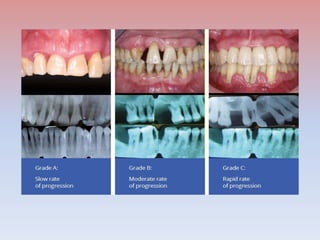

Classification of periodontitis based on grades

Papapanou et al., 2018

•Grading a periodontitis patient involves estimating the future risk of periodontitis

progression and the likely responsiveness to standard therapeutic principles.

•This estimate guides the intensity of therapy and secondary prevention after

therapy.

• Grading adds another dimension and allows the rate of progression to be

considered, using direct and indirect evidence.

• Direct evidence is based on the available longitudinal observation: for

example, in the form of older diagnostic-quality radiographs.

• Indirect evidence is based on the assessment of bone loss at the worst-

affected tooth in the dentition as a function of age.

• The periodontitis grade can then be modified by the presence of risk factors.

• Clinicians should approach grading by assuming a moderate rate of

progression (grade B) and look for direct and indirect measures of whether

there is a higher disease progression that would justify the application of

grade C.

• Grade A is applied once the disease is arrested.